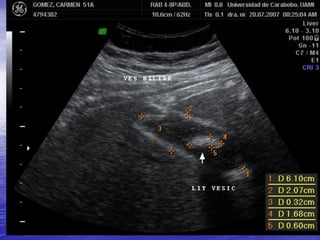

LITIASIS VESICULAR

OBSTRUCCION POR LITIASIS